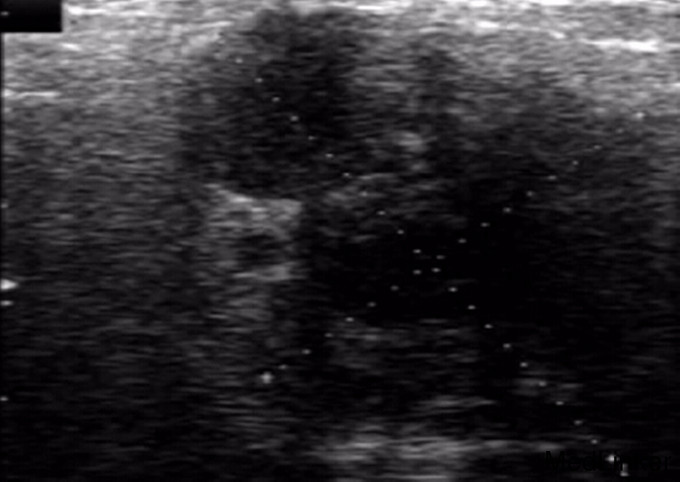

查体:右面颊腮腺区可扪及质地中等约4cm*2cm大小肿块,,界线不清,与周围组织粘连,压痛,以耳根部显著,颌下淋巴结未触及肿大,其它检查正常 辅查:超声检查:右侧腮腺内可见一个不规则低回声包块,大小约43mm*26mm*15m,边界不清,形态不规则,其内可见少许液性暗区;包块内实性部分可探及少许血流信号;MRI平扫与动态增强示:右侧腮腺区占位性病变,含囊性成分,血供欠丰富